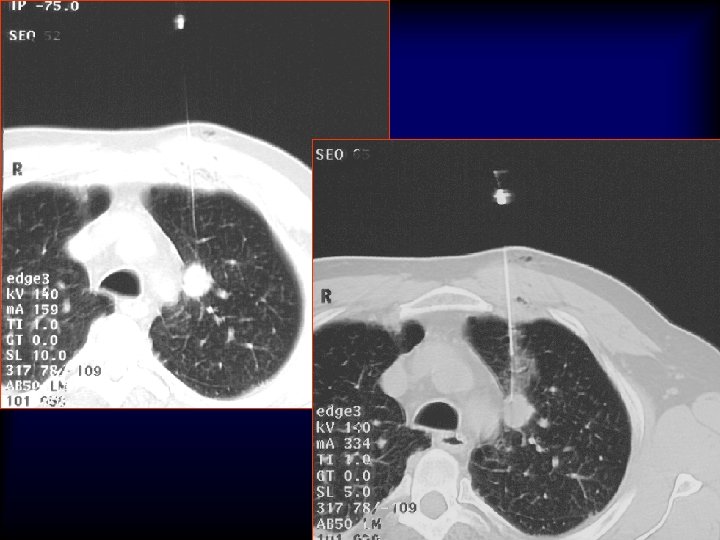

20 G/9 cm/10 T x 25 x 40 x 200 5 mm Adenocarcinoma H&E